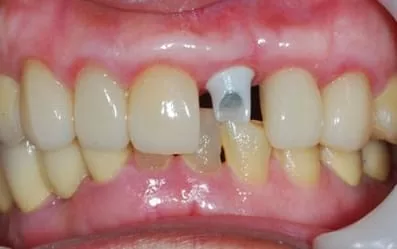

不翻瓣微創植牙:植入前檢查植體角度,再依理想位置植入Biomet 3i植體

裝上臨時柱心,不傷害鄰牙全瓷冠

不需戴活動假牙,馬上擁有固定臨時牙套